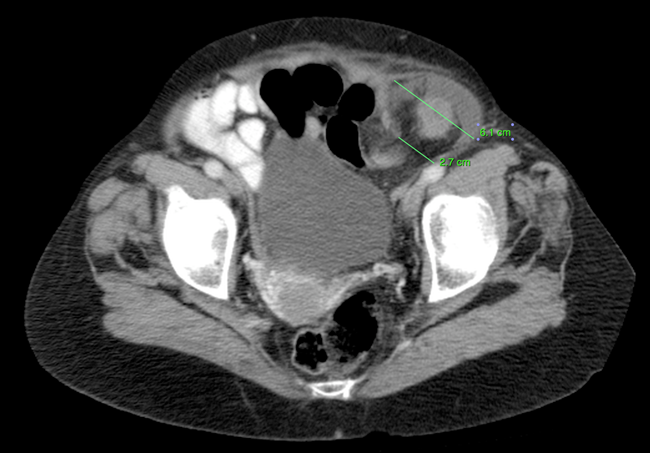

Incarcerated Inguinal Hernia